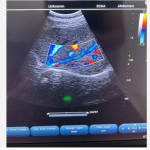

DMU11 One-stop medical supplier sale Color Doppler Notebook Ultrasound

3. Color (color multispectral) mode

4. PDI (Power Doppler) mode

5. PW (Pulse Doppler) mode

B, Dual-width, 4-width, B+M, M, B+Color, B+PDI, B+PW, PW, B+Color+PW, B+PDI+PW, ★B/BC Dual Real-time